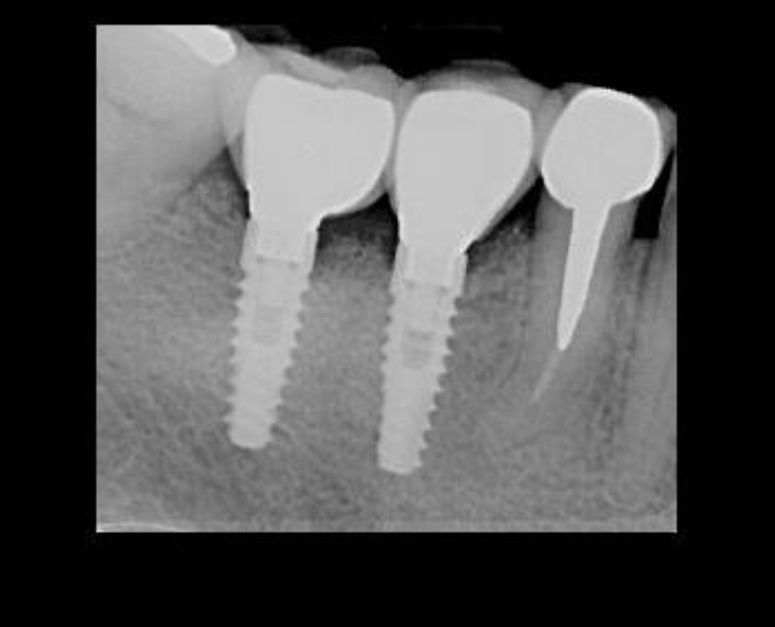

Cuento con experiencia en procedimientos de cirugía oral como: exodoncias simples, exodoncia de dientes incluidos y terceros molares, biopsias, frenillectomias, implantes dentales, implantes cigomáticos, implantes yuxtaoseos, regeneración ósea y tisular guiada.

I have experience in oral surgery procedures such as: simple extractions, extraction of impacted teeth and third molars, biopsies, frenectomies, dental implants, zygomatic implants, juxta-osseous implants, and guided bone and tissue regeneration.